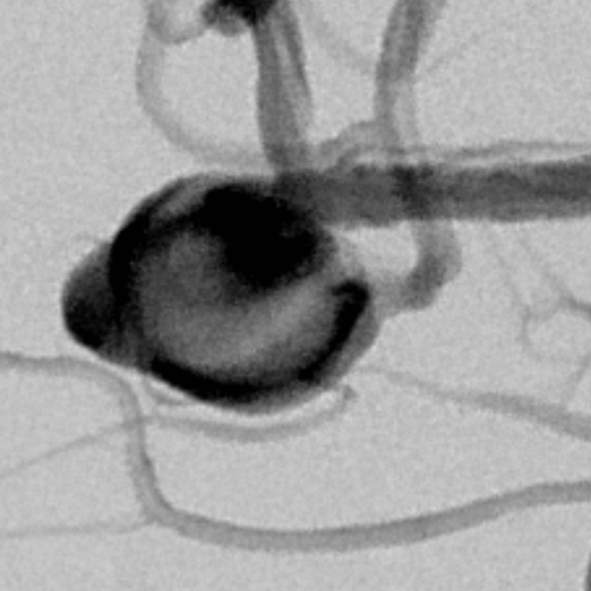

粗大分支从破裂瘤体上发出来,急性期能单纯致密栓塞吗?

最终,动脉瘤瘤体致密栓塞,各个分支保留良好